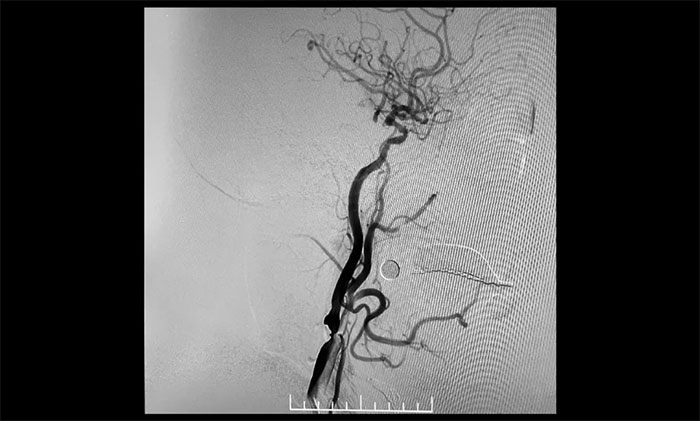

▲ 右颈内动脉起始段重度狭窄

患者为老年男性,因言语不利,伴右侧肢体活动不利入院。外院行头颅CT检查:双侧脑室旁及基底节区腔隙灶。入院后,头颅MRI平扫+DWI+MRA提示,脑干、双侧小脑及双侧大脑半球多发腔梗、缺血灶;MRA:脑动脉硬化,左侧颈内动脉不完全闭塞,右侧颈内动脉C3-C6段、右侧大脑中动脉M2段多发狭窄。“主动脉弓+全脑动脉造影”提示:右颈内动脉起始段重度狭窄,左颈内动脉起始段重度狭窄,串联左颈内动脉岩骨段中度狭窄,左颈内动脉眼动脉段闭塞。